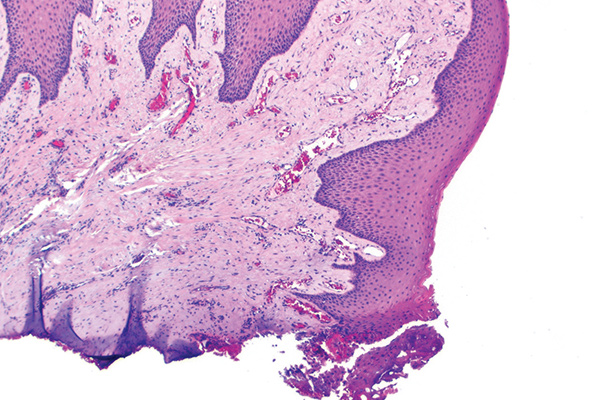

In Figure 1 through Figure 6, a variety of tissue biopsies collected via laser excision are presented. Figure 1 demonstrates the potential cellular distortion to the basement membrane region precluding detection of premalignant change. Figure 2 through Figure 4 highlight the cauterization and separation artifact caused in part by use of continuous wave versus pulsed mode. Figure 5 and Figure 6 demonstrate that by employing the advantages of laser surgical biopsy, it is possible to cleanly collect the specimen while preserving the marginal integrity of the area of suspected pathology without distortion.

Laser biopsies causing tissue cauterization and artifactual separation of the epithelium from the connective tissue (810 nm, 1 W, continuous wave).

Fig 2

Fig 3